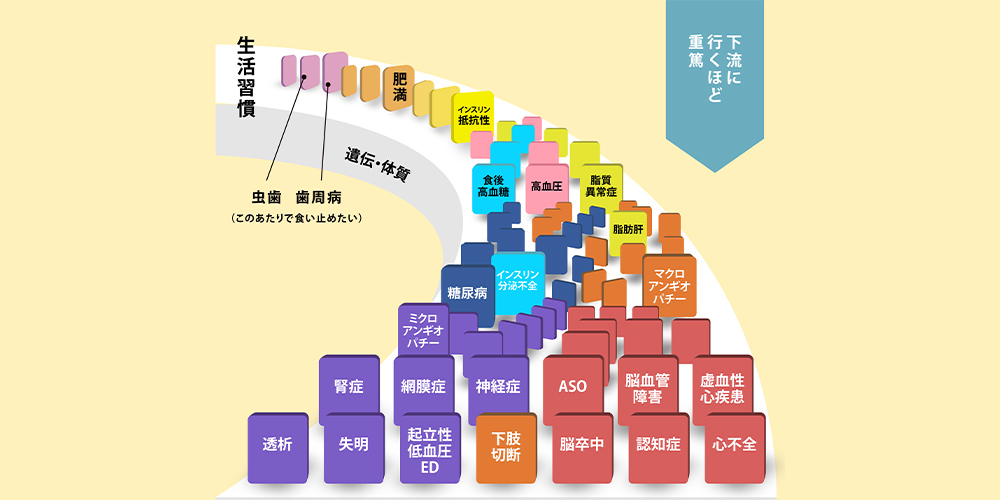

歯を失ってしまう要因の上位には、歯周病が該当します。初期段階では痛みや違和感などの自覚症状がほぼなく、いつの間にか進行してしまう厄介な疾患と言えます。歯周病の予防、および進行を食い止めるためには、日々の適切なブラッシングなどが大切ですので、ご自身でのケアをしっかりと行うように心がけましょう。